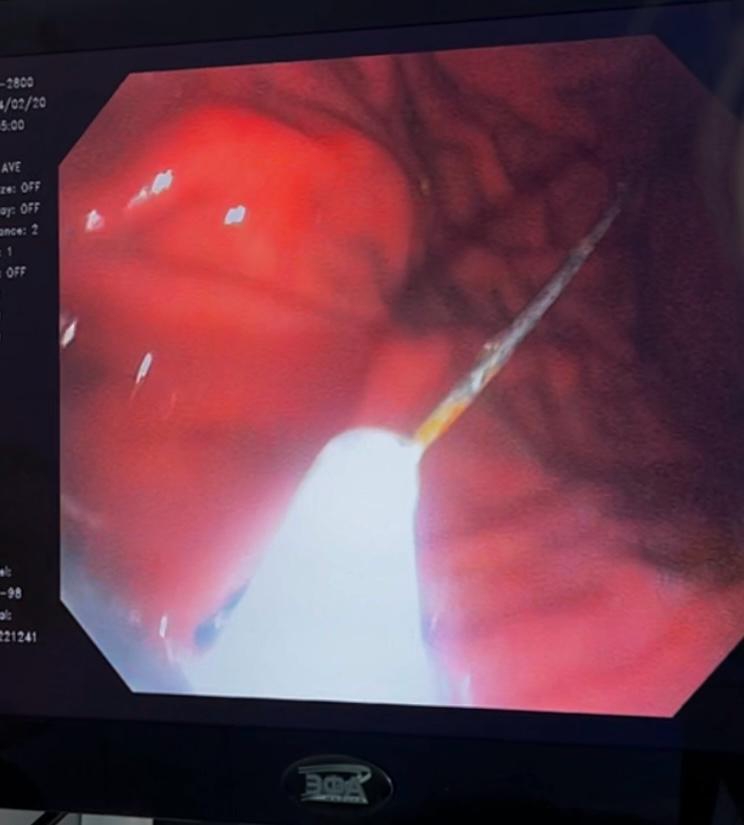

Сама пациентка рассказала, что боли появились четыре дня назад после приема пищи, по поводу чего обращалась в частные клиники к неврологу и гастроэнтерологу. Из-за отсутствия эффекта от лечения женщине выполнили эзофагогастродуоденоскопию (ЭГДС), во время которой в верхней трети тела желудка обнаружили швейную иглу.

Пациентку госпитализировали в горбольницу, где ей провел эндоскопическое удаление инородного тела из желудка. Иглу в 3,2 см удалось без последствий извлечь из желудка.